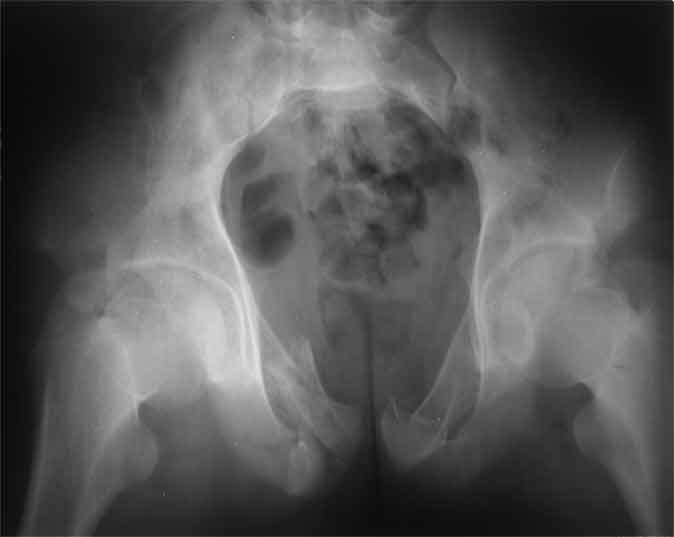

А чего там собственно таинственного? Билатеральное ротационно-нестабильное повреждение таза, перелом крестца в I зоне (по Denis)справа,частичное повреждение левого КПС, оскольчатые переломы лонной, седалищной костей справа (В3.2). Повреждение достаточно стабильное + молодой возраст+ сроки - оперативного лечения не требует.

Не смог разглядеть на представленных картинках частичное повреждение левого КП, повреждение Денис1-2 справа? 3Д реконструкции в инлет и боковой проекциях убедительно не демонстрируют типа повреждения задних отделов тазового кольца(справа боковая масса скомпремирована), Наверное, у тебя есть возможность оценить тип перелома крестца по прямой проекции 3Д.

по Pennal et al.- латеральное компрессионное повреждение тип В(ротационно-нестабильное (внутренняя ротация), вертикально стабильное)

по Tile classif. тип В2-1 - частично стабильное повреждение с неполным разрывом задней дуги.

По вертлуге- смог разглядеть только изолированный перелом передней колонны.

Насколько я понял из твоего письма, обращенного к анонимному vit, ты не видишь показаний к реконструкции перелома. Я бы взялся за реконструкцию(илео-ингвинальный доступ), хоть прошел и месяц после травмы: боковая 3Д показывает смещение нагрузочной зоны впадины, что однозначно будет способствовать разрушению хряща головки и впадины( особенно у 16 летнего пациента с ожидаемым высоким уровнем активности) + изменение геометрии впадины за счет неустраненного смещения фрагментов колонны (КТ, 3Д данные).

На мой взгляд, без реконструкции этот сустав обречен (концепция вторичной конгруэтности в данных условиях работать не будет), реконструкция дает шанс на восстановление функции сустава.

По представленным материалам, мне кажется, перелом был передней колонны ацетабулум с минимальным вовлечением нагрузочной поверхности сустава, левосторенний повреждение КПС и лонных костей.